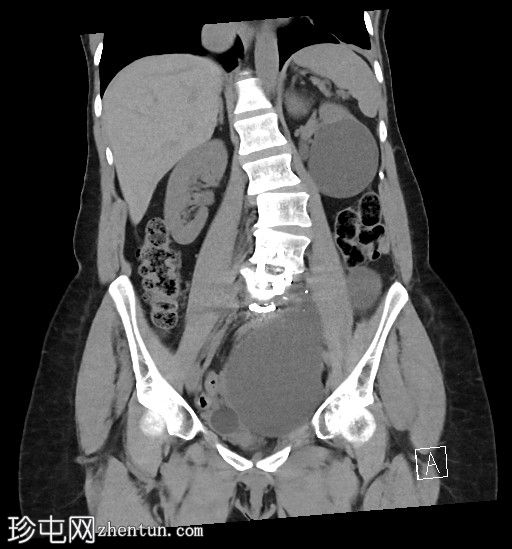

冠状位

平扫

左侧腹膜后可见一巨大囊性肿块,位于左侧腰大肌内侧,紧邻多个手术夹(ALIF手术所用),这些手术夹紧贴囊性肿块后壁。

膀胱已行引流管减压,并被囊性肿块向右侧推移。

子宫和左侧附件在囊性肿块前方保持正常的脂肪间隙,因此附件囊性病变的可能性较小。

左侧输尿管难以辨认,因为它位于囊性肿块下缘后方。